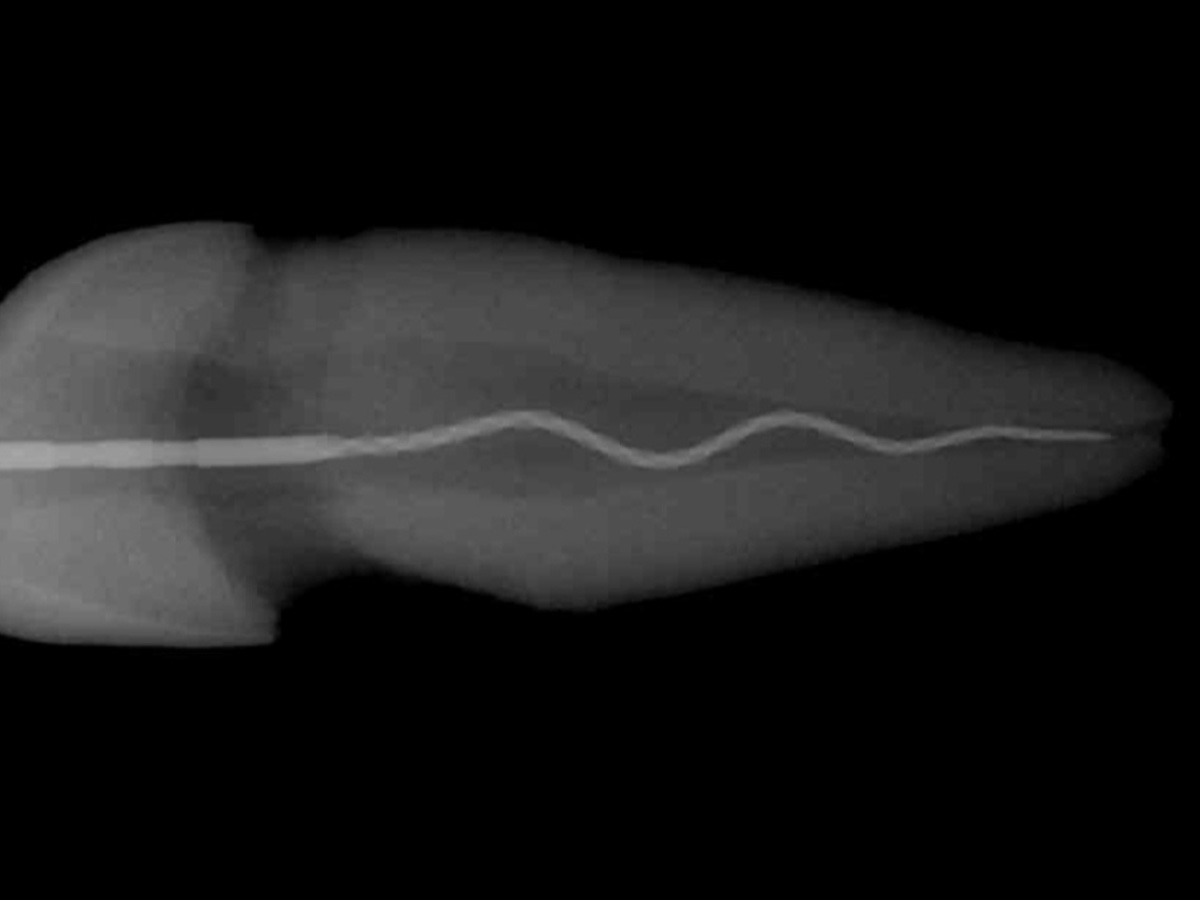

• Warm-VertikaleKondensation

• Kalt-Hydraulische Kondensation

• Vorhersagbare Wurzelfüllung bei unterschiedlichen Kanalkonfigurationen